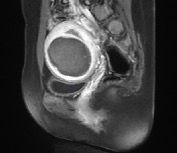

Imaging Outcomes

Figure 4. (A-D). Contrast-enhanced MRI obtained from a 35-year old patient with uterine fibroid. (A). Pre-HIFU MRI showed a significant enhancement of a uterine fibroid located at the anterior wall of the uterus, and the size of the fibroid was 5.6 cm x 4.6 cm x 4.9 cm; (B).1-day post-HIFU MRI showed no enhancement of the treated fibroid, the uterine fibroid was completely ablated; (C). 4-month post HIFU MRI showed the size of the treated fibroid reduced to 5.0 cm x 4.3 cm x 4.2cm, the shrinkage was 28.5%; (D). 10-month post-HIFU MRI showed the size of the treated fibroid reduced to 3.5 cm x 3.0 cm x 3.2cm, and the shrinkage was 73.4% compared to baseline. Images courtesy Prof. Zhang Lien.